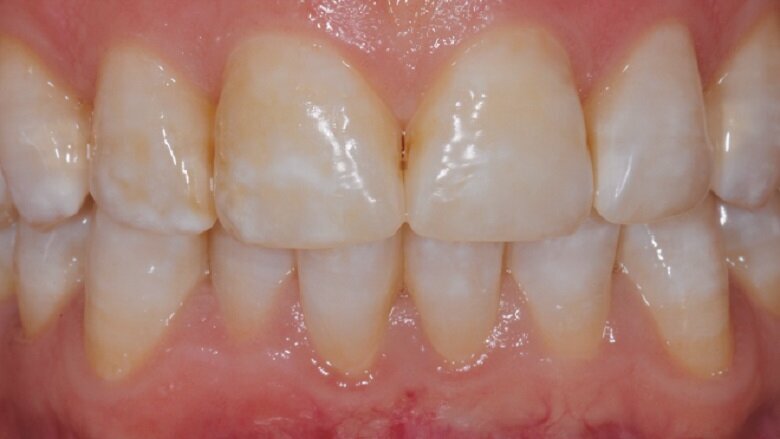

Slika 2: Po 30 dneh.

Pacientka je izkazala visoko stopnjo sodelovanja pri zdravljenju in po predpisanem protokolu, opazila je tudi klinične izboljšave, pa ne le po videzu (fotografiji na slikah 2 in 3 sta posneti po 30 in 70 dneh), temveč tudi glede občutka, tako da je poročala o zmanjšani občutljivosti zob. Pri pregledih lahko opazimo izboljšanje indeksa zobnih oblog ter zmanjšano poroznost zaradi izboljšanja teksture sklenine in dentina.